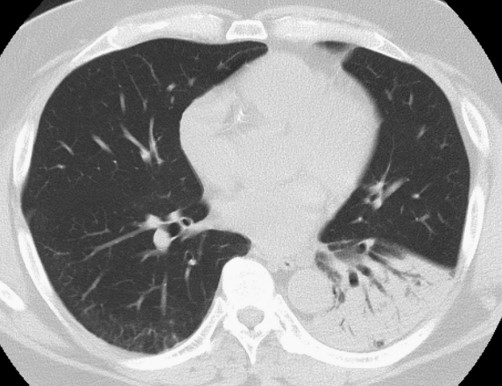

• 骨折后呼吸困難,警惕肺脂肪栓塞︱病例分享

骨折后呼吸困難,警惕肺脂肪栓塞︱病例分享

醫脈通編譯整理,未經授權請勿轉載。病例資料患者,男,61歲,跌倒后骨折,于急診室就診,并在數小時內出現進行性加重的呼吸急促。入院時,患者無發熱,血壓正常,室內空氣下血氧飽和度為92%,意識清楚,無局灶性神經功能缺損的癥狀或體征。其左下肢和右上肢畸形。既往病史無特殊。患者左下肢X線片顯示腓骨和脛骨骨折。胸片顯示上肺葉雙側肺泡混濁,這些不明確的斑片狀氣腔模糊是非